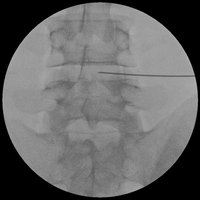

内服薬の効果が少ない場合は神経根ブロックという注射を行うことがあります。エックス線透視下にモニター画面を見ながら腰部神経根周囲に局所麻酔薬を注入します。この方法は痛みを軽減させるとともに、多くの神経根の中から痛みの原因となっている神経根を確認するという診断の意味もあります。残念ながら1回の注射で永続的に痛みを取り除くことは難しいのですが、効果を見ながら複数回注射を繰り返すことで痛みが軽減する場合があります。

18年8月にコンドリアーゼ(商品名ヘルニコア)という薬品が販売されました。これは椎間板内の髄核という成分を選択的に分解する酵素です。この酵素を椎間板内に注入して椎間板の内圧を減少させることで、椎間板ヘルニアの症状を軽減するというのが椎間板内酵素注入療法の原理です。神経根ブロックと同様にエックス線透視下にモニター画面を見ながら椎間板内に針を挿入し酵素を注入します。約15分で終了しますが、注入後の体調の変化がないかを観察するために1泊入院します。その治療成績については、酵素注入を受けた人の7割が注入後3週間以内に症状が軽減したという報告があります。